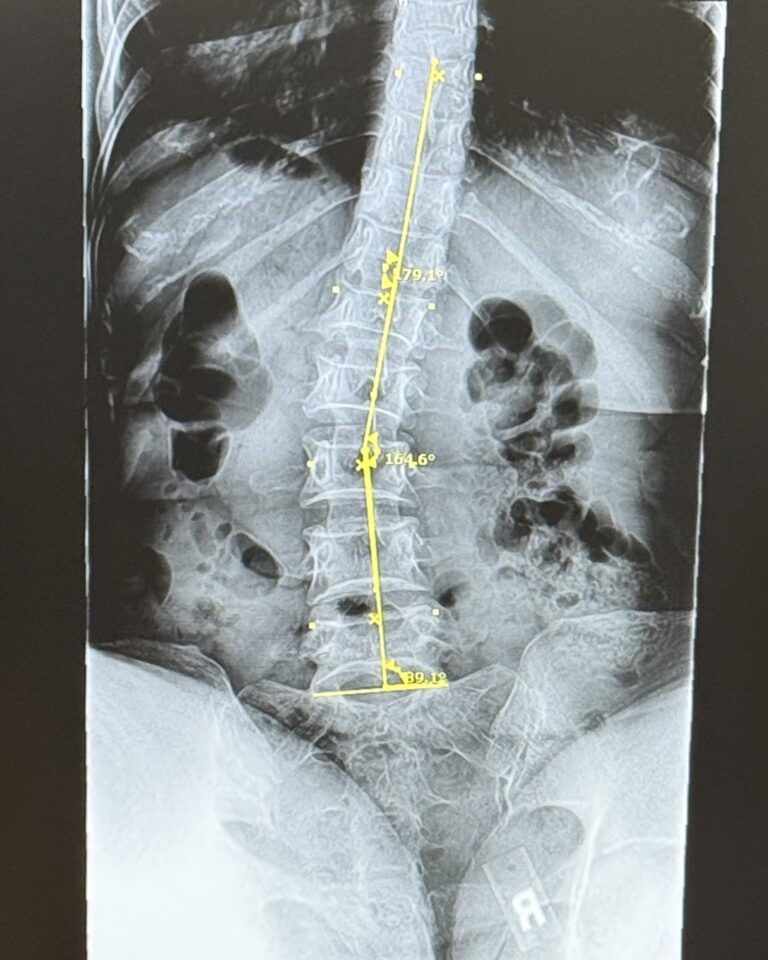

Finally, things made sense. One targeted MRI still showed nothing, but a nuclear bone scan lit up both feet—proof that my pain was real. The weight of being dismissed for years was finally lifted!